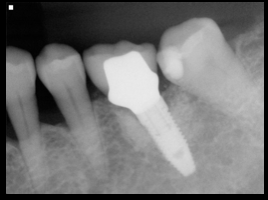

治療法

- 上顎右側前歯にインプラントを1本抜歯即時に埋入し、

- オールセラミックにて被せ物を行なった。

- 下顎左側臼歯に1本のインプラントを待時に埋入し、オールセラミッククランにて被せ物を行なった。

治療結果

- 審美的な仕上がりで、患者自身も満足した。15年経過し良好である。

現在は2〜3ヶ月おきのメインテナンス中である。

治療を行う上での 注意点 (リスク・副作用)

オールセラミックには欠け易いといったリスクがあるためナイトガードは必須である。

インプラントの周囲は特に清掃が重要である。